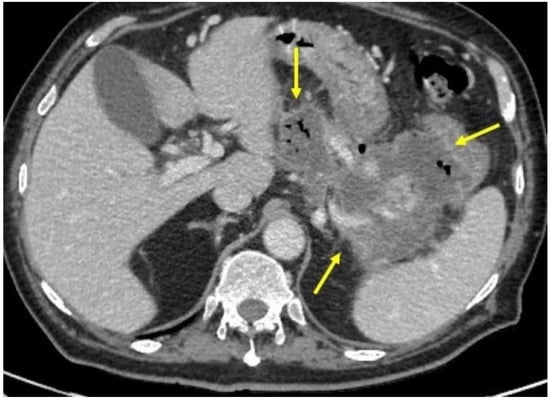

Approximately two months after the hospitalization, they returned to the hospital with epigastric pain and fever (38 °C). Laboratory results showed a WBC count of 14,530/mm3 (neutrophils: 78%) and a CRP level of 163 mg/L (<5 mg/L), procalcitonin 0.14 ng/mL. Pancreatic enzymes and liver function test results were within the normal ranges. An abdominal CT scan showed the presence of multiple confluent fluid collections extending from the head to the tail along the entire pancreatic profile containing air (Figure 1). An endoscopic investigation and an endoscopic ultrasound (EUS) were performed. The upper endoscopy revealed the presence of a fistula opening of about 8 mm in diameter in the duodenum bulb with leakage of purulent material (Figure 2). EUS showed the presence of air in the fistula and a complex 5 cm fluid collection in the tail of the pancreas (Figure 3). An abdominal CT scan with gastrografin confirmed the fistulous channel originating from the first duodenal portion, which gives rise to two branches, anteriorly in the head of the pancreas and posteriorly in the tail. After a collegial reunion with clinicians, surgeons, radiologists, and gastroenterologists, it was decided to proceed with the drainage of the larger pancreatic collection in an attempt to heal the fistula with the duodenum. EUS-guided trans gastric drainage of the fluid collection was performed using a 16 × 20 mm lumen-apposing metal stent (LAMS, Hot-Spaxus, Taewoong Medical Co., Gimpo, Korea), obtaining drainage of copious purulent material in the stomach (Figure 4).

Figure 1.

Abdominal CT scan showing the presence of multiple confluent fluid collections extending from the head to the tail along the entire pancreatic profile (outlined from yellow arrow).